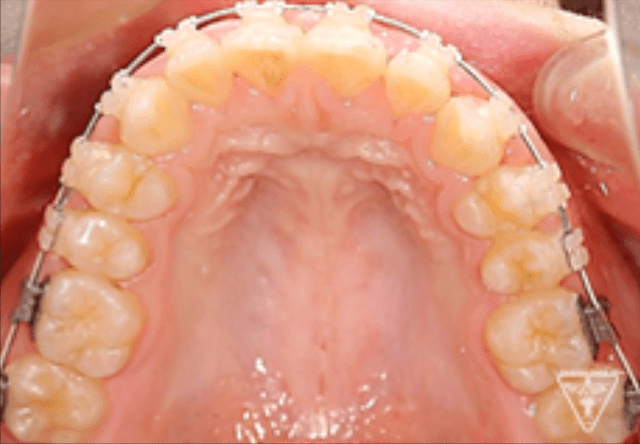

矯正器具 装着時の治療過程

後期